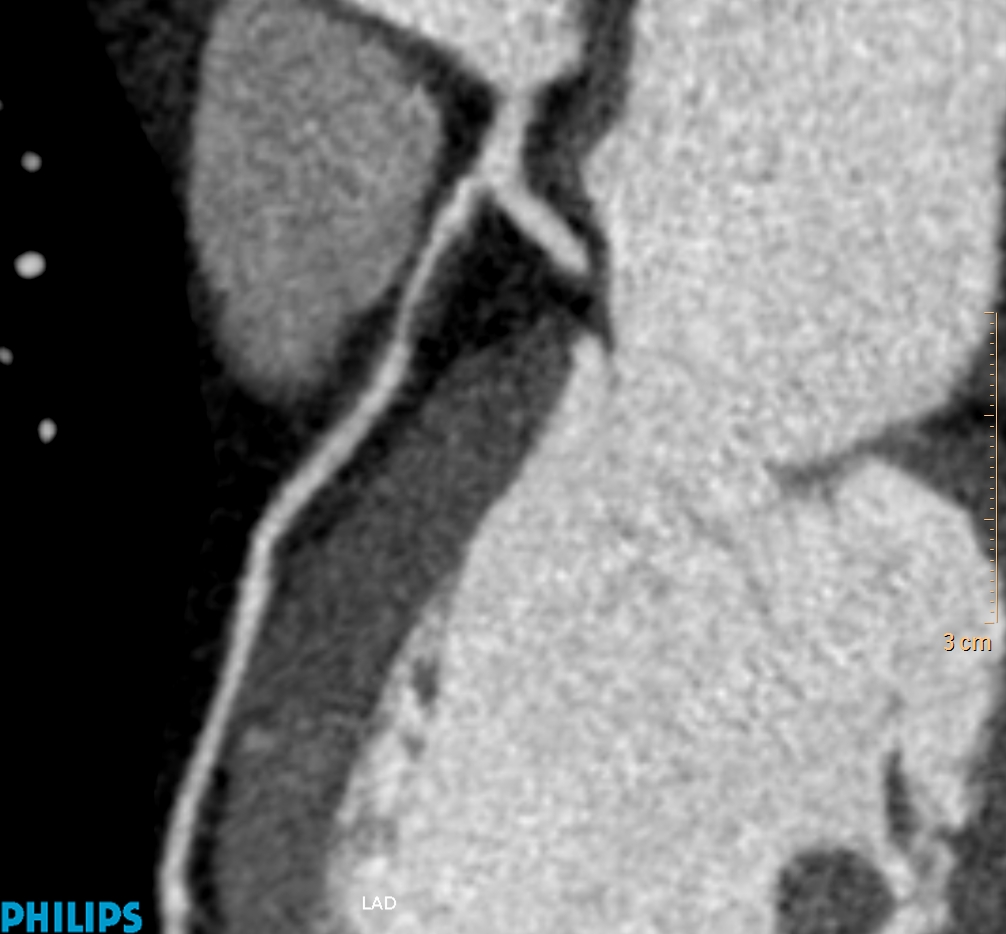

Τρισδιάστατη και δισδιάστατη απεικόνιση των στεφανιαίων αγγείων όπου διακρίνεται σημαντική στένωση λίγο μετά την έκφυσή του πρόσθιου κατιόντα κλάδου